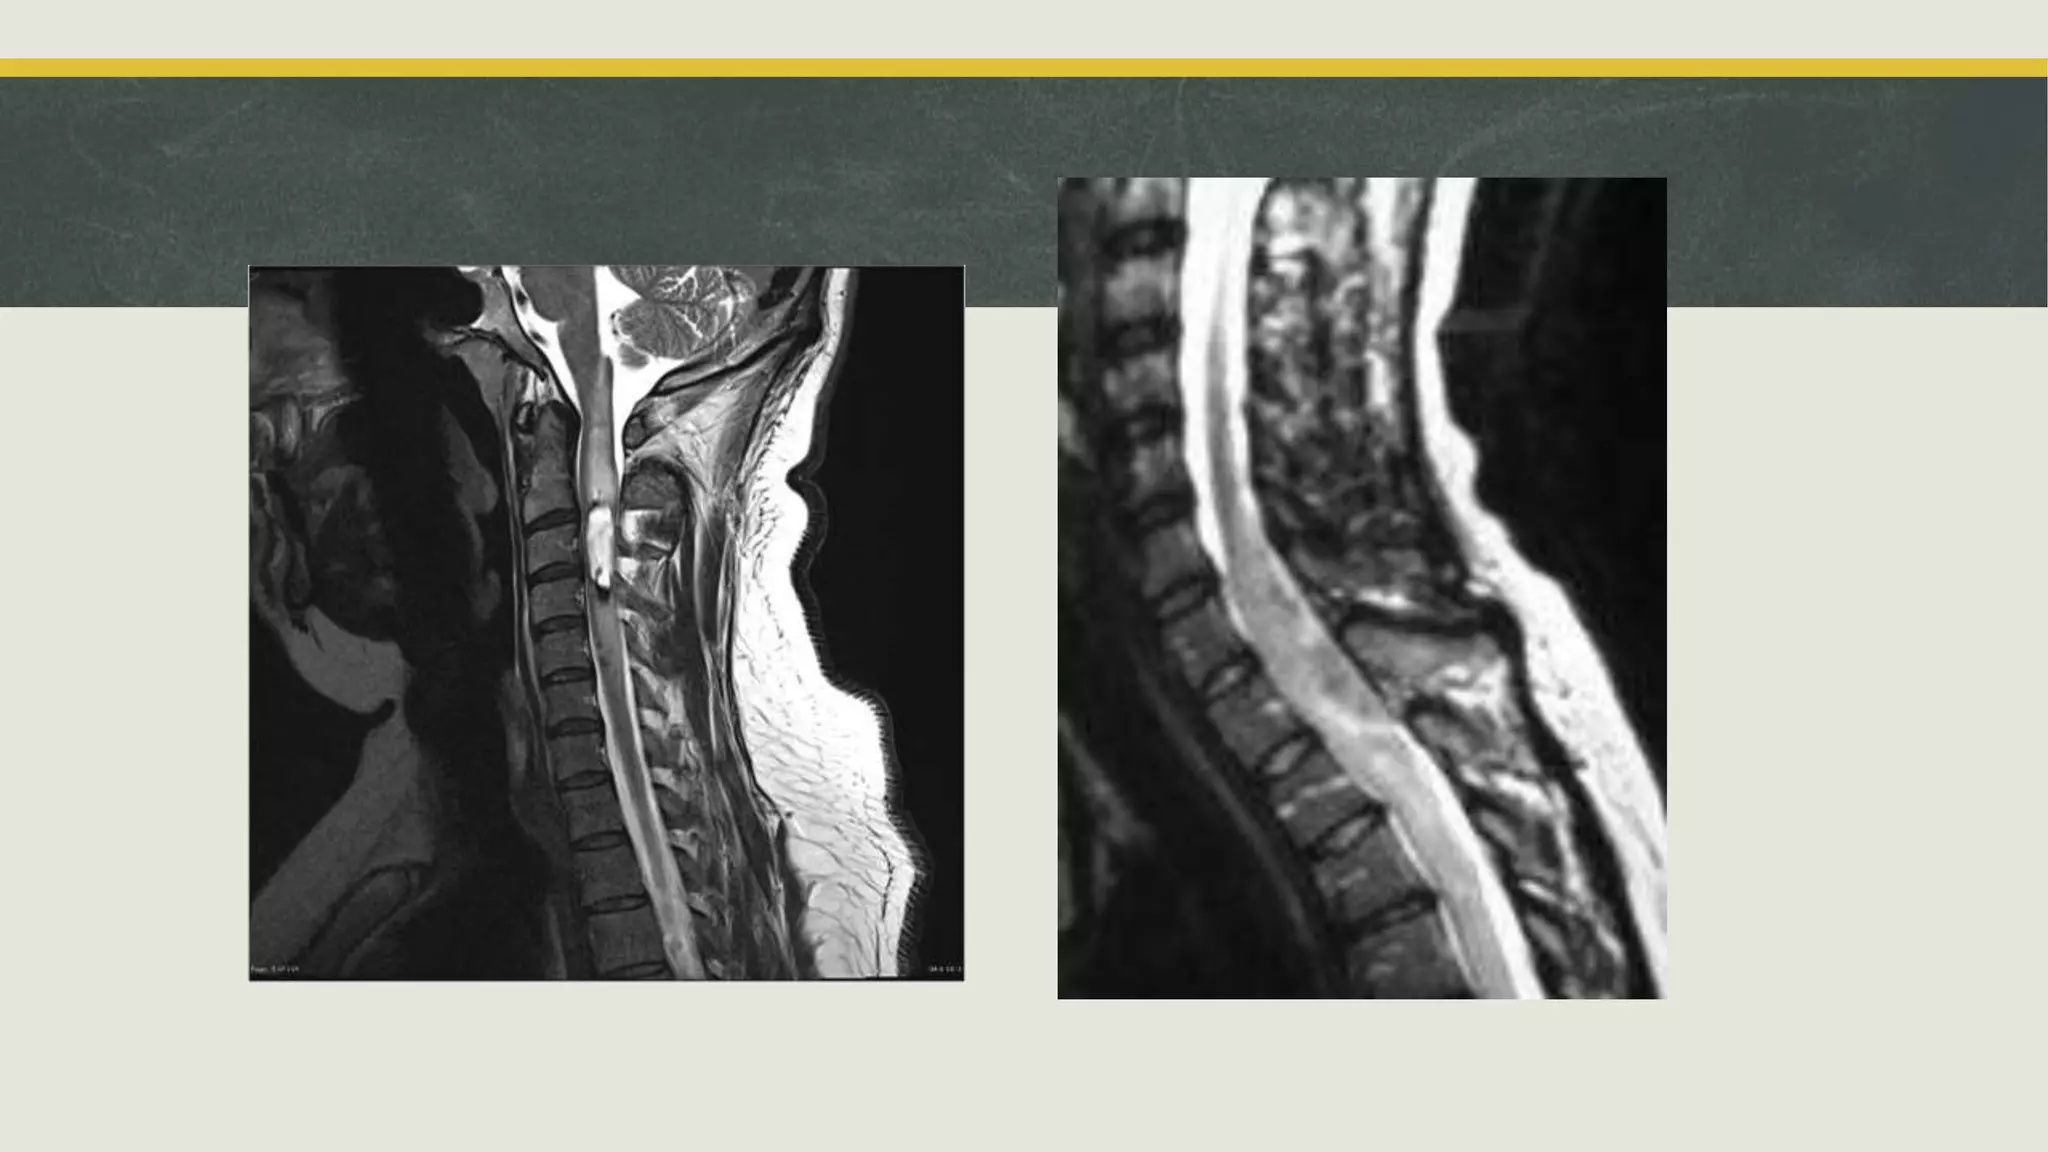

Оношлогоо

 MRI CT

Оношлогоо  Нүдний угийгдурандах  MRI CT  Тархины цахилгаан бичлэг  Тархи нугасны шингэн